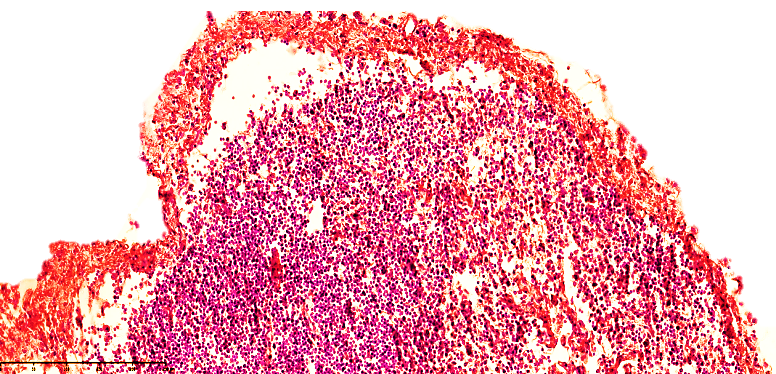

Microscopic examination of regional lymph nodes in infants who died of peritonitis at 28 days of age revealed that the immature medullary and medullary layers were not fully formed, and changes that occurred as a result of severe large-scale purulent and non-purulent inflammation, such as necrotic enterocolitis, before the development of peritonitis led to changes in the lymphatic drainage system in the form of blockage or paralysis.This, in turn, was manifested by a sharp tightening of the capsule in the mesenteric lymph nodes of 28-day-old infants, a sharp expansion of the subcapsular spaces, which were significantly enlarged. In particular, in the development of peritonitis, a sharp decrease in the function of lymphatic drainage mainly leads to the accumulation of exudate fluid in the abdominal cavity. Hyperproduction of mesothelial cells and the formation of multifocal desquamation foci, many erosive foci were also detected in the visceral sheets.In the mesenteric lymphatic vessels, a sharp slowdown in the drainage function of lymphostasis is observed, which is explained by the expansion of the vessels and the increase in size of the fluid accumulated due to plasmarrhagia in the regional lymph nodes. As a result, the capsules of the lymph nodes are stretched, the subcapsular spaces expand, and lymphostasis develops. Eosinophilic inclusions of varying degrees of light and dark staining in the cortex and medulla of the lymph node: cellular components, various tissue parts with destructive changes were detected. The lymph nodes have a swollen appearance, the capsule is tense, and the subcapsular spaces are filled with lymphatic fluid (see Figure 1). Secondary lymphoid follicles are not detected, the germinal center is quiet, the location of lymphocytes in the cortical and paracortical areas of the active areas of the lymph nodes is reduced compared to normal, and in the active areas of the cortex, foci of lymphocytes migrating towards the postcapillary venules are detected. In the direction of the cerebral bands of the medulla, it is determined that a swelling appearance in the areas of the lymphatic gate and a variable mixture of lymphocytes and other types of cells (macrophages, dendritic cells, interdigitating cells, fibroblasts, histiocytes, reticulocytes, etc.) are relatively preserved in the areas of the reticulum and trabeculae of the brain bands. | Figure 1. Mesenteric lymph node of a 28-day-old infant with peritonitis. Treated for 10 days. The lymph node capsule is of variable width, the subcapsular space is dilated, and lymphoid follicles are not identified. Small vessels are fully visible. Stained with GE. Size 10x10 |